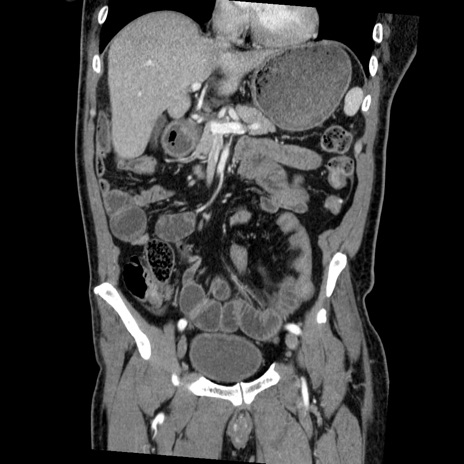

症例22(冠状断像)

【症例】50歳代男性

【主訴】腹痛

【現病歴】AVMからの被殻出血のため回復期リハ病棟入院中。 本日午後3時頃急に下腹部痛が出現した。

【既往歴】AVM、被殻出血、虫垂炎、高血圧

【身体所見】意識晴明、左半身不全麻痺、会話の理解は良好、36.5°C、腹部:膨隆、全体に板状硬、下腹部正中に圧痛点あり、反跳痛-、筋性防御不明、右下腹部にope scar

【データ】WBC 9400、CRP 0.06